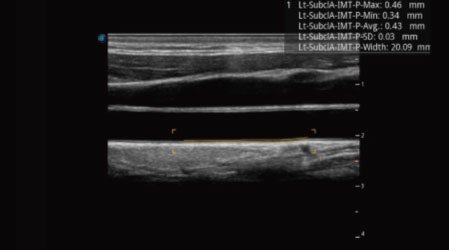

Auto IMT

Auto IMT makes the measurement of anterior and posterior intima-media thickness much easier with simple placement of the ROI.